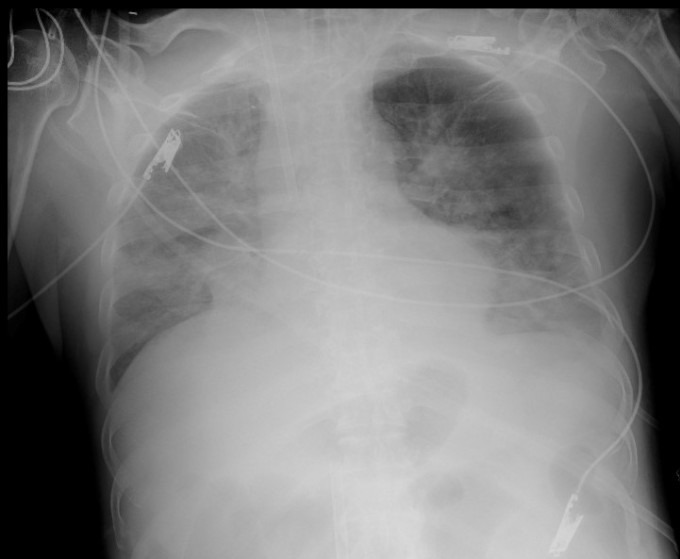

Ông được đưa đến Bệnh viện đa khoa tỉnh Ninh Bình cấp cứu cuối tháng 5, trong tình trạng sốc nặng, phổi co thắt nhiều, suy hô hấp phải thở máy và duy trì vận mạch liều rất cao, sau đó chuyển đến Bệnh viện Bạch Mai.

Bác sĩ Nguyễn Bá Cường, Trung tâm Hồi sức tích cực, Bệnh viện Bạch Mai, ngày 6/6 cho biết phổi bệnh nhân không còn đảm bảo được chức năng thông khí ngay cả khi hỗ trợ máy thở tối đa. Bệnh nhân phải thở ECMO (thiết bị oxy hóa qua màng ngoài cơ thể) phương tiện hỗ trợ hô hấp cuối cùng kèm các biện pháp hồi sức tích cực.

Kết quả nội soi phế quản bệnh nhân phát hiện các mảng giả mạc thùy dưới phổi hai bên (màng viêm màu trắng đục), nghi nhiễm nấm. Một ngày sau, giả mạc phát triển trên toàn bộ niêm mạc đường thở tạo nên các đám sùi và đan xen nhau như mạng nhện lấp kín hết lòng khí phế quản. Kết quả nhuộm soi các mẫu bệnh phẩm đường thở đều có nấm sợi. Hình ảnh giải phẫu bệnh giả mạc cũng cho thấy nấm tập trung nhiều thành đám. Bác sĩ kết luận bệnh nhân bị nhiễm nấm Aspergillus fumigatus sau khi ăn mối.

Phim chụp X-quang phổi bệnh nhân ngày 30/5. Ảnh: Bệnh viện cung cấp